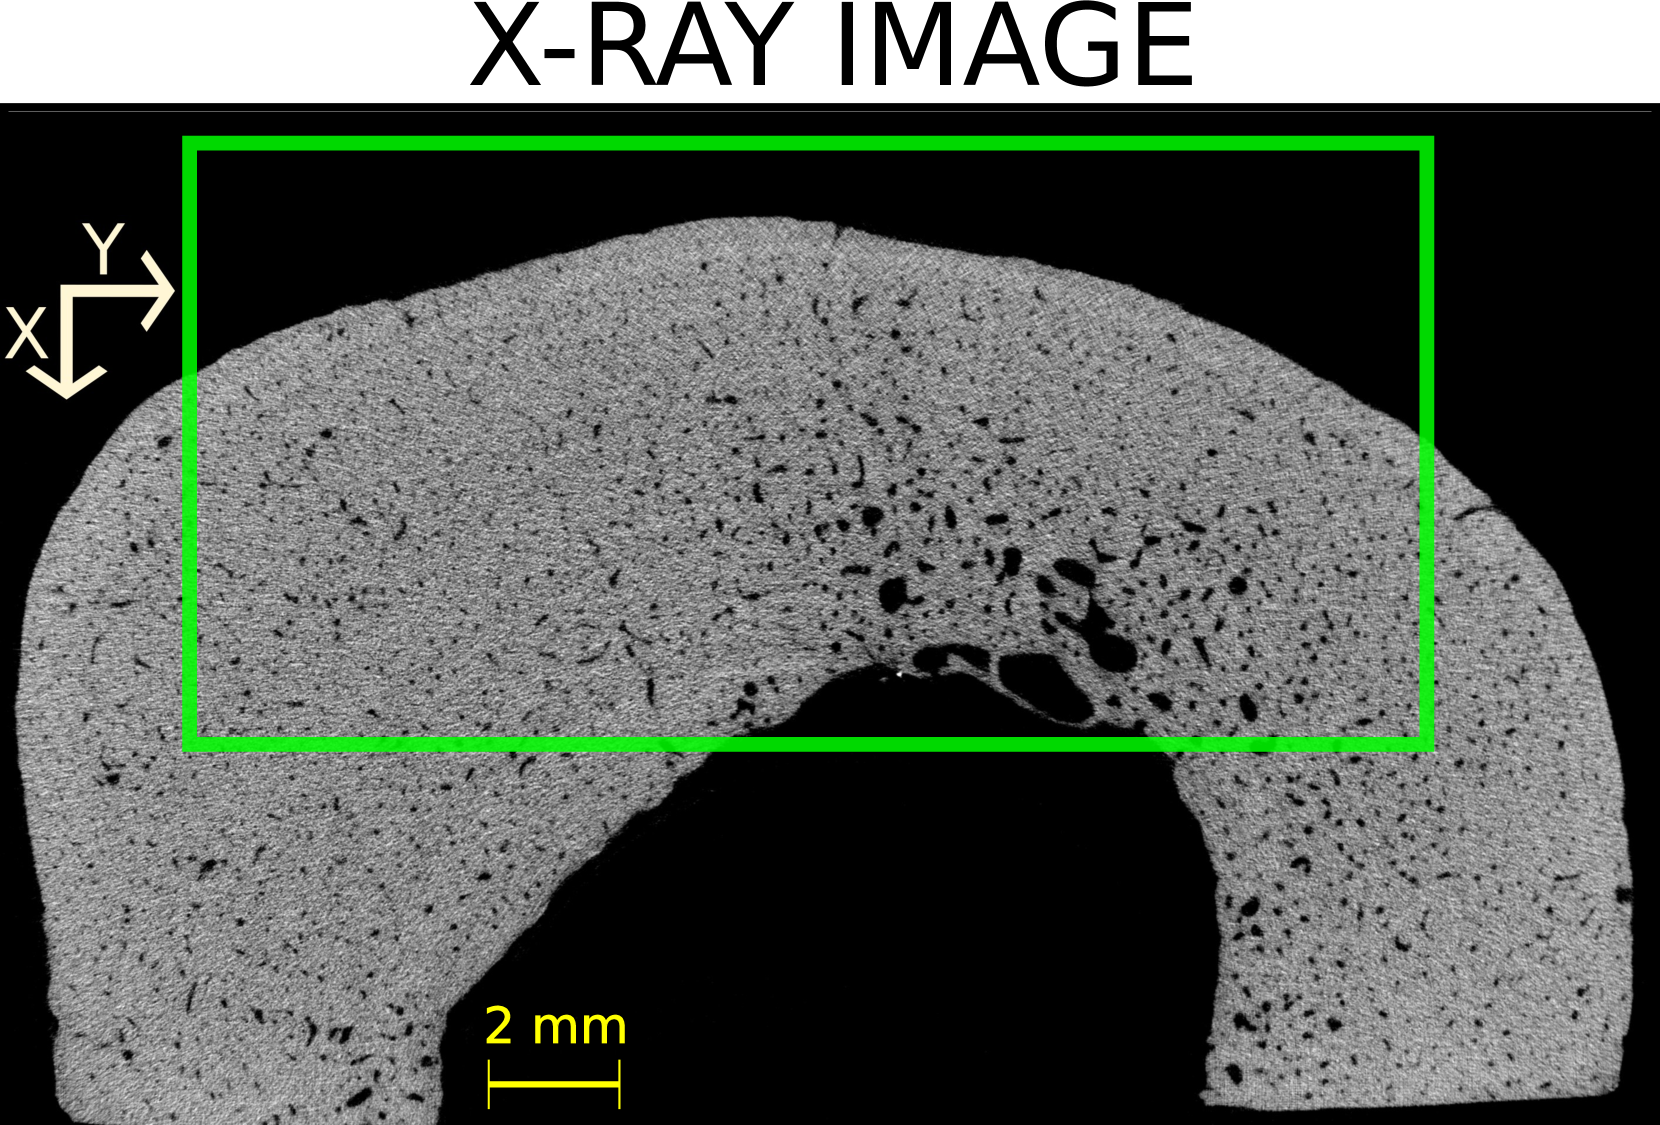

Four volumes of interest (VOI) were defined within the three-dimensional (3D) HR-µCT image of each sample. The thickness (direction of the bone axis) and width of the VOIs were 15 and 20 mm, respectively. The height of the VOIs varied between 8 and 10 mm, depending on the cortical thickness and diameter of each sample. Figure LABEL:method:example_xray_slice shows a two-dimensional (2D) slice in the transverse plane extracted from each VOI for all the samples. The VOI’s dimensions approximately correspond to the thickness (probe elevation direction), lateral dimension (probe aperture) and depth of the US image.

The initial step was to apply a Gaussian filter (round kernel of radius 2 or 3, depending on the sample) to remove acquisition noise. Then, the VOI were binarized using 3D Otsu method [31]. Given that this study focuses on the cortical bone tissue, we removed, in the endosteal region, the bone remnants resulting from a trabecularization [5] of the cortex (samples 4 and 5, see Figure LABEL:method:example_xray_slice and Figure S1 in supplementary materials). To do this, we used kernel filtering (either Kuwahara or Uniform kernels with a radius of 2) and morphological operations to close all pores below a specific threshold diameters, thereby generating a mask that excluded trabecular regions. The specific choice of kernel and parameters varied across samples to accommodate the high morphological variability among the samples (Figure LABEL:method:example_xray_slice).

The 20 VOIs (4 VOIs in each of the 5 samples) showed a great diversity in terms of cortical thickness, porosity, and distribution of pores (Figure LABEL:method:example_xray_slice). Cortical thickness estimated from micro-CT images ranged from 2.5 to 6.3 mm (Table LABEL:table_chap_4:pore_stat_samples_combined). The microstructure parameters are summarized in Table LABEL:table_chap_4:pore_stat_samples_combined. Samples 1 and 2 had the lowest porosity (5–6.4 % and 5.3–6.7 %, respectively) and no large pores (Lg.Po.Dm 175 m). Sample 3 showed moderate porosity (7–12.3 %) with moderately large pores (Lg.Po.Dm in the range 224–228 m). Samples 4 and 5 presented the highest porosity (12.2–16 % and 16.4–16.6 %, respectively) with 10% of the pores with diameter above 300 m. Sample 4 displayed the largest pores (Lg.Po.Dm in the ranged 334–423 m), which can be clearly seen in Figure LABEL:method:example_xray_slice. Porosity values and the porosity gradient from the periosteal to the endosteal surface seen in some samples are consistent with the literature data for elderly donors [27].